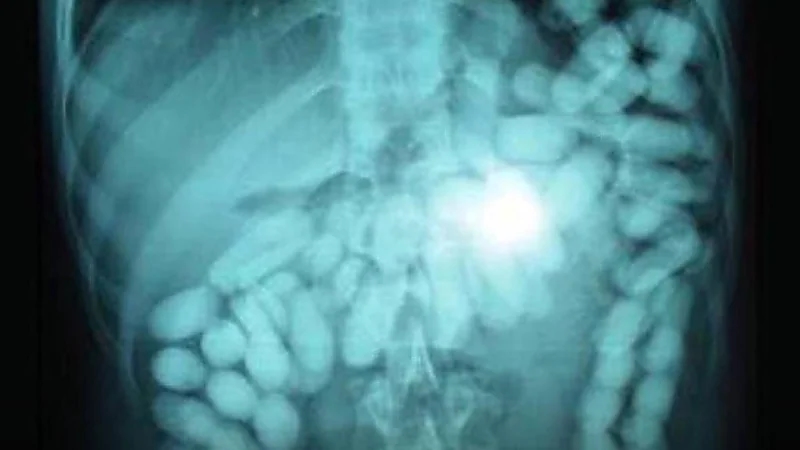

الأردن تضبط مسافر ابتلع 826 حبة كبتاجون ليتمكن من تهريبها إلى المملكة